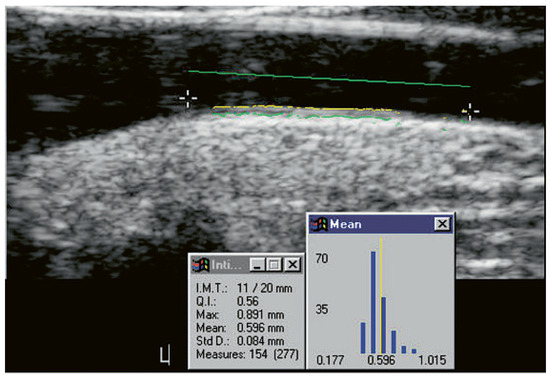

Cardiovascular Risk Prediction with Ultrasound

by Michèle Depairon, Roger Darioli and Michel Romanens

Cardiovasc. Med. 2010, 13(9), 255; https://doi.org/10.4414/cvm.2010.01523 - 15 Sep 2010

This paper addresses primary care physicians, cardiologists, internists, angiologists and doctors desirous of improving vascular risk prediction in primary care. Many cardiovascular risk factors act aggressively on the arterial wall and result in atherosclerosis and atherothrombosis. Cardiovascular prognosis derived from ultrasound imaging is, however, excellent in subjects without formation of intimal thickening or atheromas. Since ultrasound visualises the arterial wall directly, the information derived from the arterial wall may add independent incremental information to the knowledge of risk derived from global risk assessment. This paper provides an overview on plaque imaging for vascular risk prediction in two parts: Part 1: Carotid IMT is frequently used as a surrogate marker for outcome in intervention studies addressing rather large cohorts of subjects. Carotid IMT as a risk prediction tool for the prevention of acute myocardial infarction and stroke has been extensively studied in many patients since 1987, and has yielded incremental hazard ratios for these cardiovascular events independently of established cardiovascular risk factors. However, carotid IMT measurements are not used uniformly and therefore still lack widely accepted standardisation. Hence, at an individual, practicebased level, carotid IMT is not recommended as a risk assessment tool. The total plaque area of the carotid arteries (TPA) is a measure of the global plaque burden within both carotid arteries. It was recently shown in a large Norwegian cohort involving over 6000 subjects that TPA is a very good predictor for future myocardial infarction in women with an area under the curve (AUC) using a receiver operating curves (ROC) value of 0.73 (in men: 0.63). Further, the AUC for risk prediction is high both for vascular death in a vascular prevention clinic group (AUC 0.77) and fatal or nonfatal myocardial infarction in a true primary care group (AUC 0.79). Since TPA has acceptable reproducibility, allows calculation of posttest risk and is easily obtained at low cost, this risk assessment tool may come in for more widespread use in the future and also serve as a tool for atherosclerosis tracking and guidance for intensity of preventive therapy. However, more studies with TPA are needed. Part 2: Carotid and femoral plaque formation as detected by ultrasound offers a global view of the extent of atherosclerosis. Several prospective cohort studies have shown that cardiovascular risk prediction is greater for plaques than for carotid IMT. The number of arterial beds affected by significant atheromas may simply be added numerically to derive additional information on the risk of vascular events. A new atherosclerosis burden score (ABS) simply calculates the sum of carotid and femoral plaques encountered during ultrasound scanning. ABS correlates well and independently with the presence of coronary atherosclerosis and stenosis as measured by invasive coronary angiogram. However, the prognostic power of ABS as an independent marker of risk still needs to be elucidated in prospective studies. In summary, the large number of ways to measure atherosclerosis and related changes in human arteries by ultrasound indicates that this technology is not yet sufficiently perfected and needs more standardisation and workup on clearly defined outcome studies before it can be recommended as a practice-based additional risk modifier. Full article

Show Figures

Figure 1